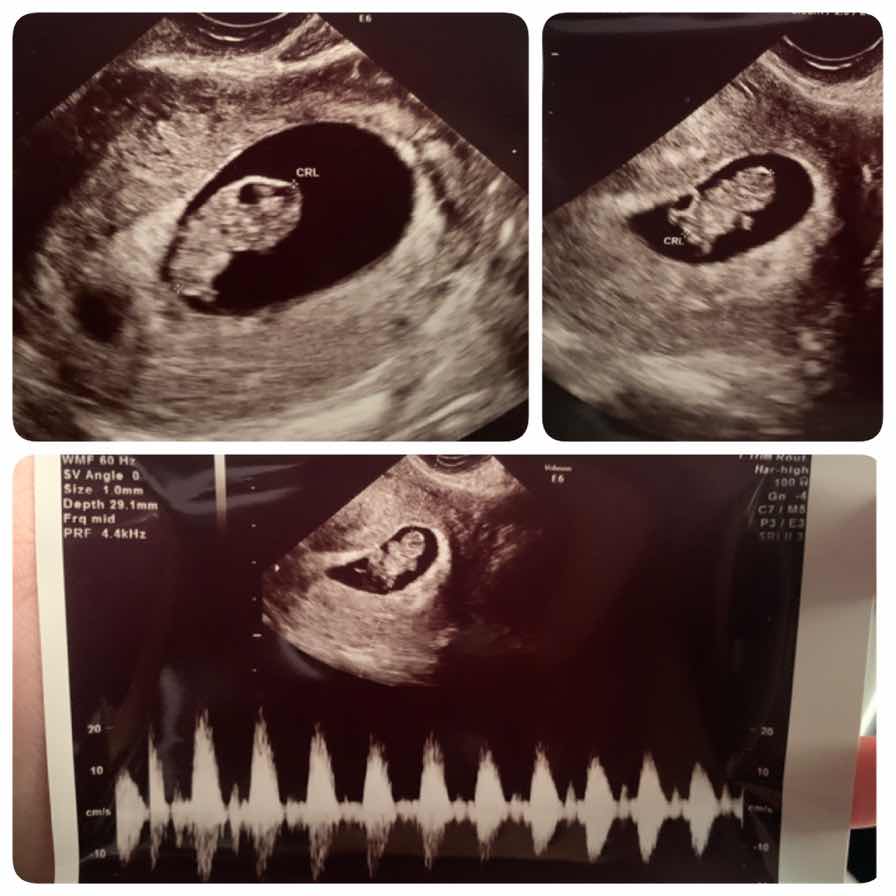

บ้านนี้ 8week ตัวเล็กไปมั้ยค่ะ☺️

บ้านนี้8week เหมือนกันจ้า กำหนดคลอด 23 ส.ค.